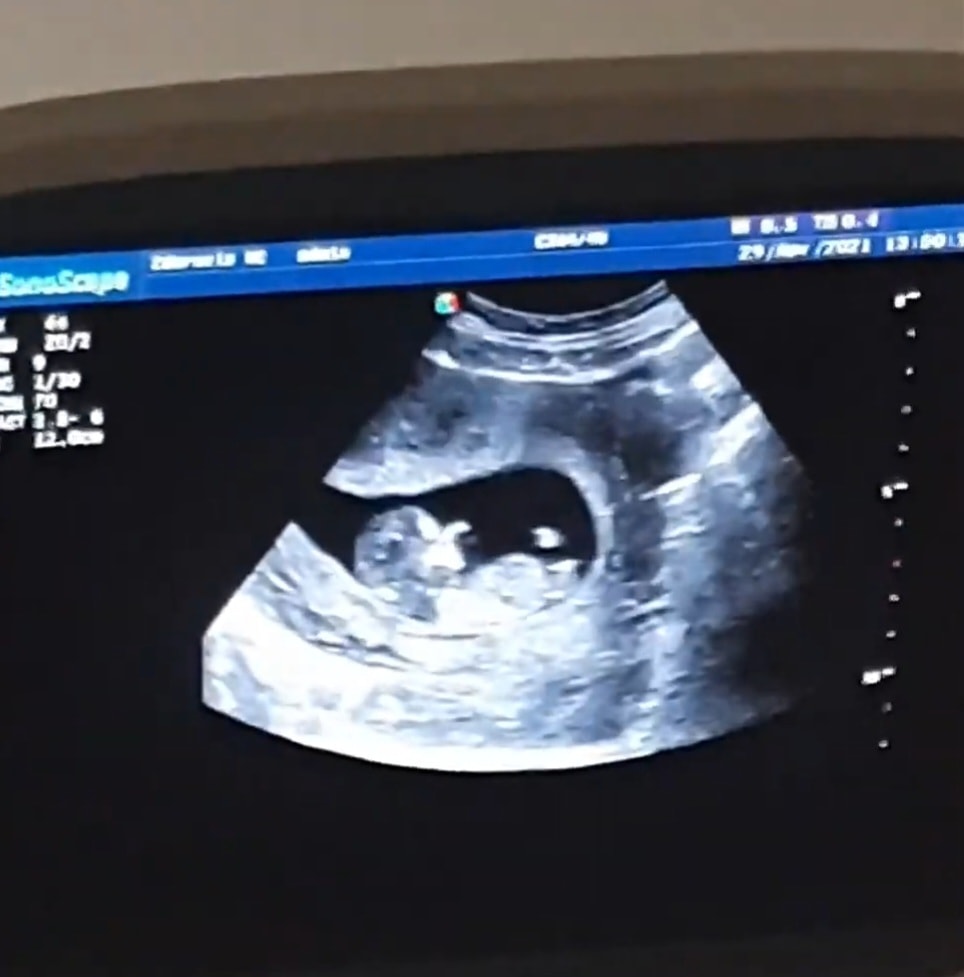

А это сейчас

два врача говорят что больше похоже на мальчика но очень сомневаются, что думаете?)

второй фото - сейчас 🙂

Если то, что видно около попки малыша - половой бугорок, то я бы предположила, что это девочка, он строго параллелен позвоночнику

На втором фото нет полового бугорка, это торчит ножка. По нему не определить пол.